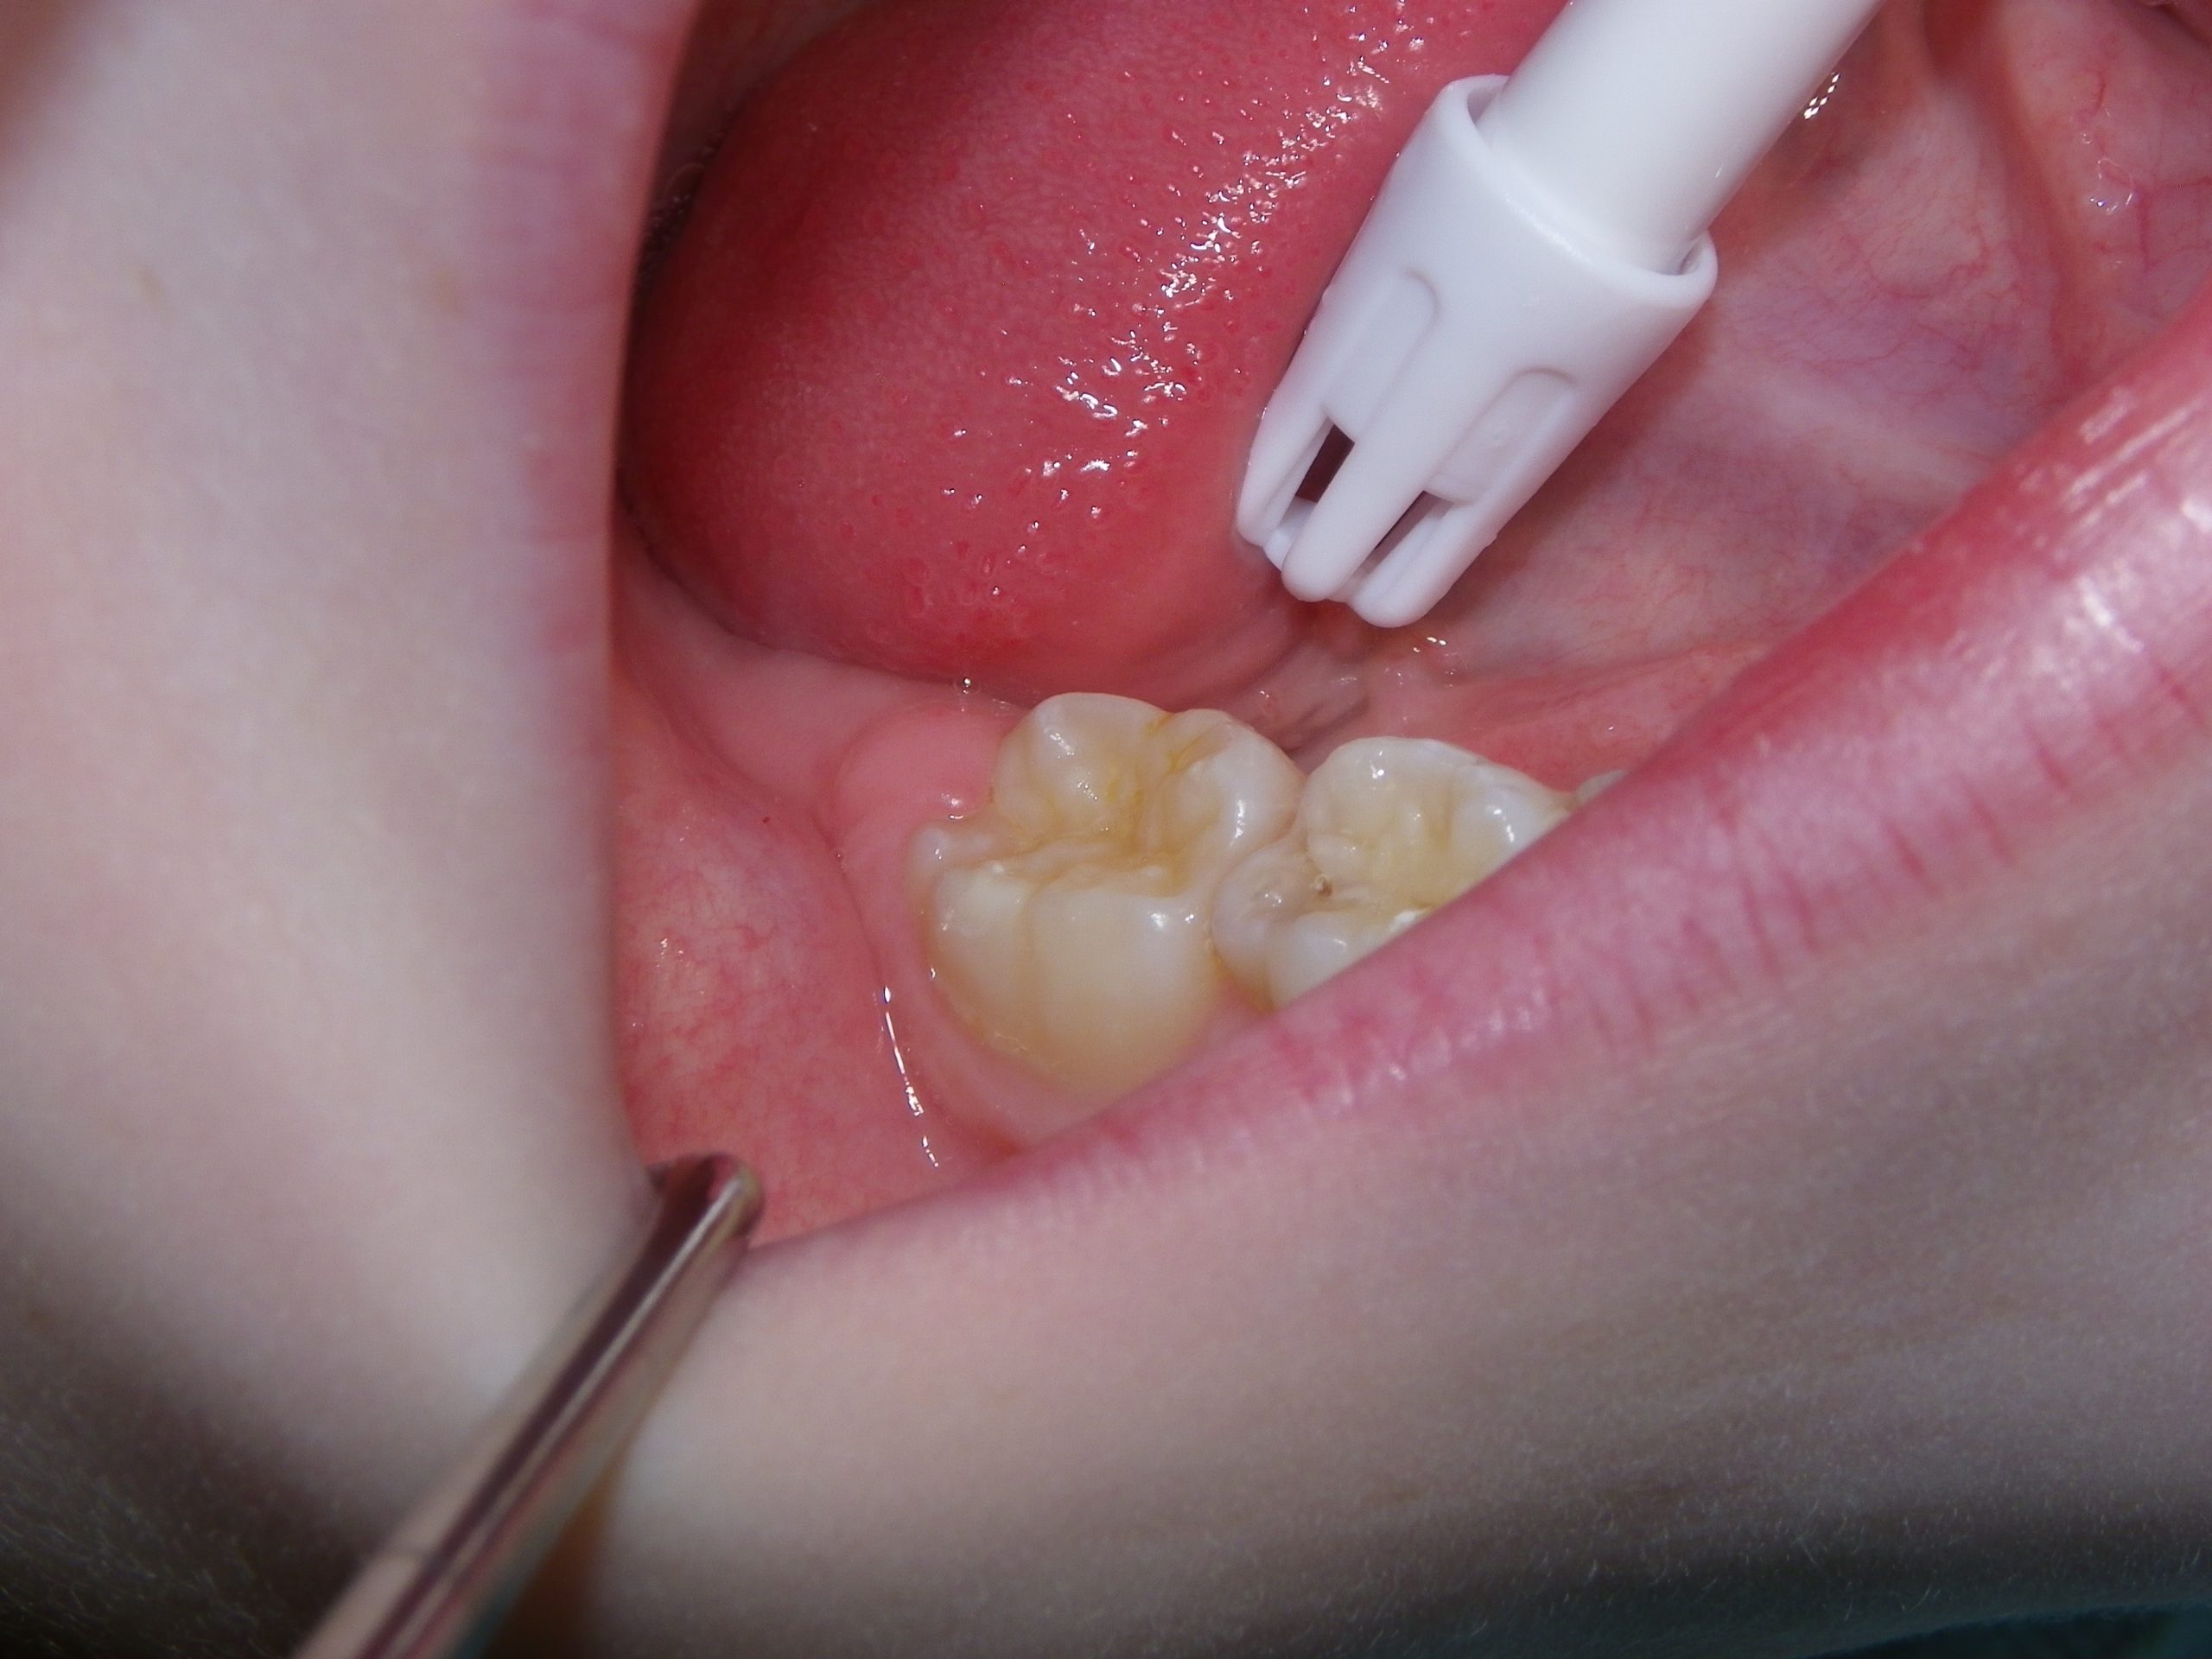

This quick photo series shows the step-by-step process of placing a sealant onto the grooves of an adult molar of a six-year-old. First, air abrasion is used to mechanically remove any loose surface debris or contaminants. Secondly, an acid gel is applied to the surface to be sealed. Finally, a sealant is applied to the surface and allowed to set. For the sharp-eyed, the sealant used was GC Fuji Triage, a glass ionomer sealant that while not as wear-resistant as the more commonly used resin sealants, is more moisture-friendly (ie: contamination resistant) and releases fluoride. The fluoride release allows the underlying enamel to be strengthened over time, making it more decay-resistant for the future.